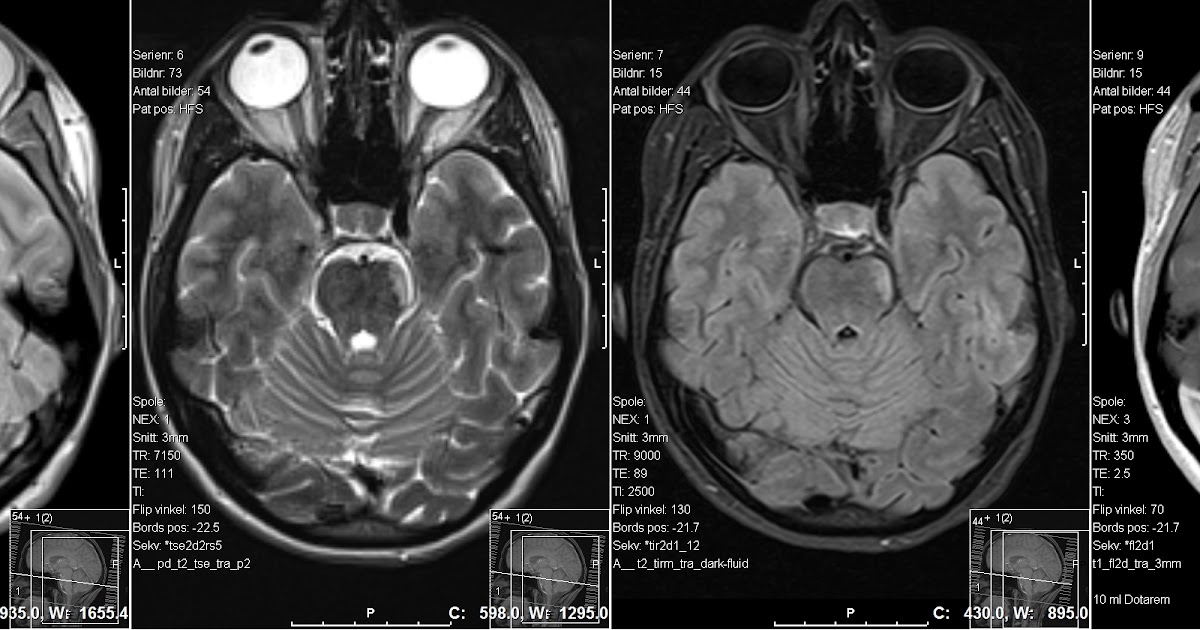

21+ Multiple Sclerosis Ct Scan Pictures. Ct scans may be used to exclude other causes of neurologic impairment, but they have a low positive predictive value in the diagnosis of ms; I also went on to have an abnormal mri a few weeks later.

So would the ct scan have shown signs of multiple sclerosis? Overview signs and symptoms conditions that suggest it contributing risk factors conditions suggested by it what else it can lead to. Ct scans may be used to exclude other causes of neurologic impairment, but they have a low positive predictive value in the diagnosis of ms;

Magnetic resonance imaging (mri) usually reveals many more lesions than the ct multiple sclerosis: Waking up day after day knowing you are stricken with ms that gradually drags you, healthy young person, toward chronic illness and. Magnetic resonance imaging (mri) usually reveals many more lesions than the ct multiple sclerosis: Learn the causes, early signs, and symptoms.